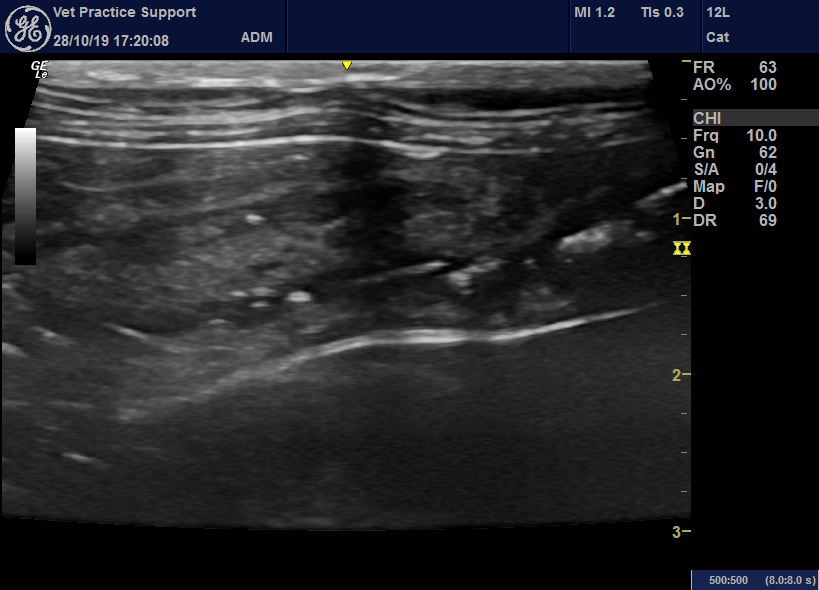

From www.vetpracticesupport.com

An acute enterocolitis in cats with striking sonographic features is Cat Intestinal Wall Thickening What is feline inflammatory bowel disease? Abdominal palpation (gently using the hands to feel the internal organs) can allow your veterinarian to detect organ enlargement,. 45,56 the bright mucosal speckling has been. As inflammatory cells invade, the. Ibd in cats occurs when the walls of the digestive tract become thickened and inflamed, reducing its ability to function properly. Or the. Cat Intestinal Wall Thickening.